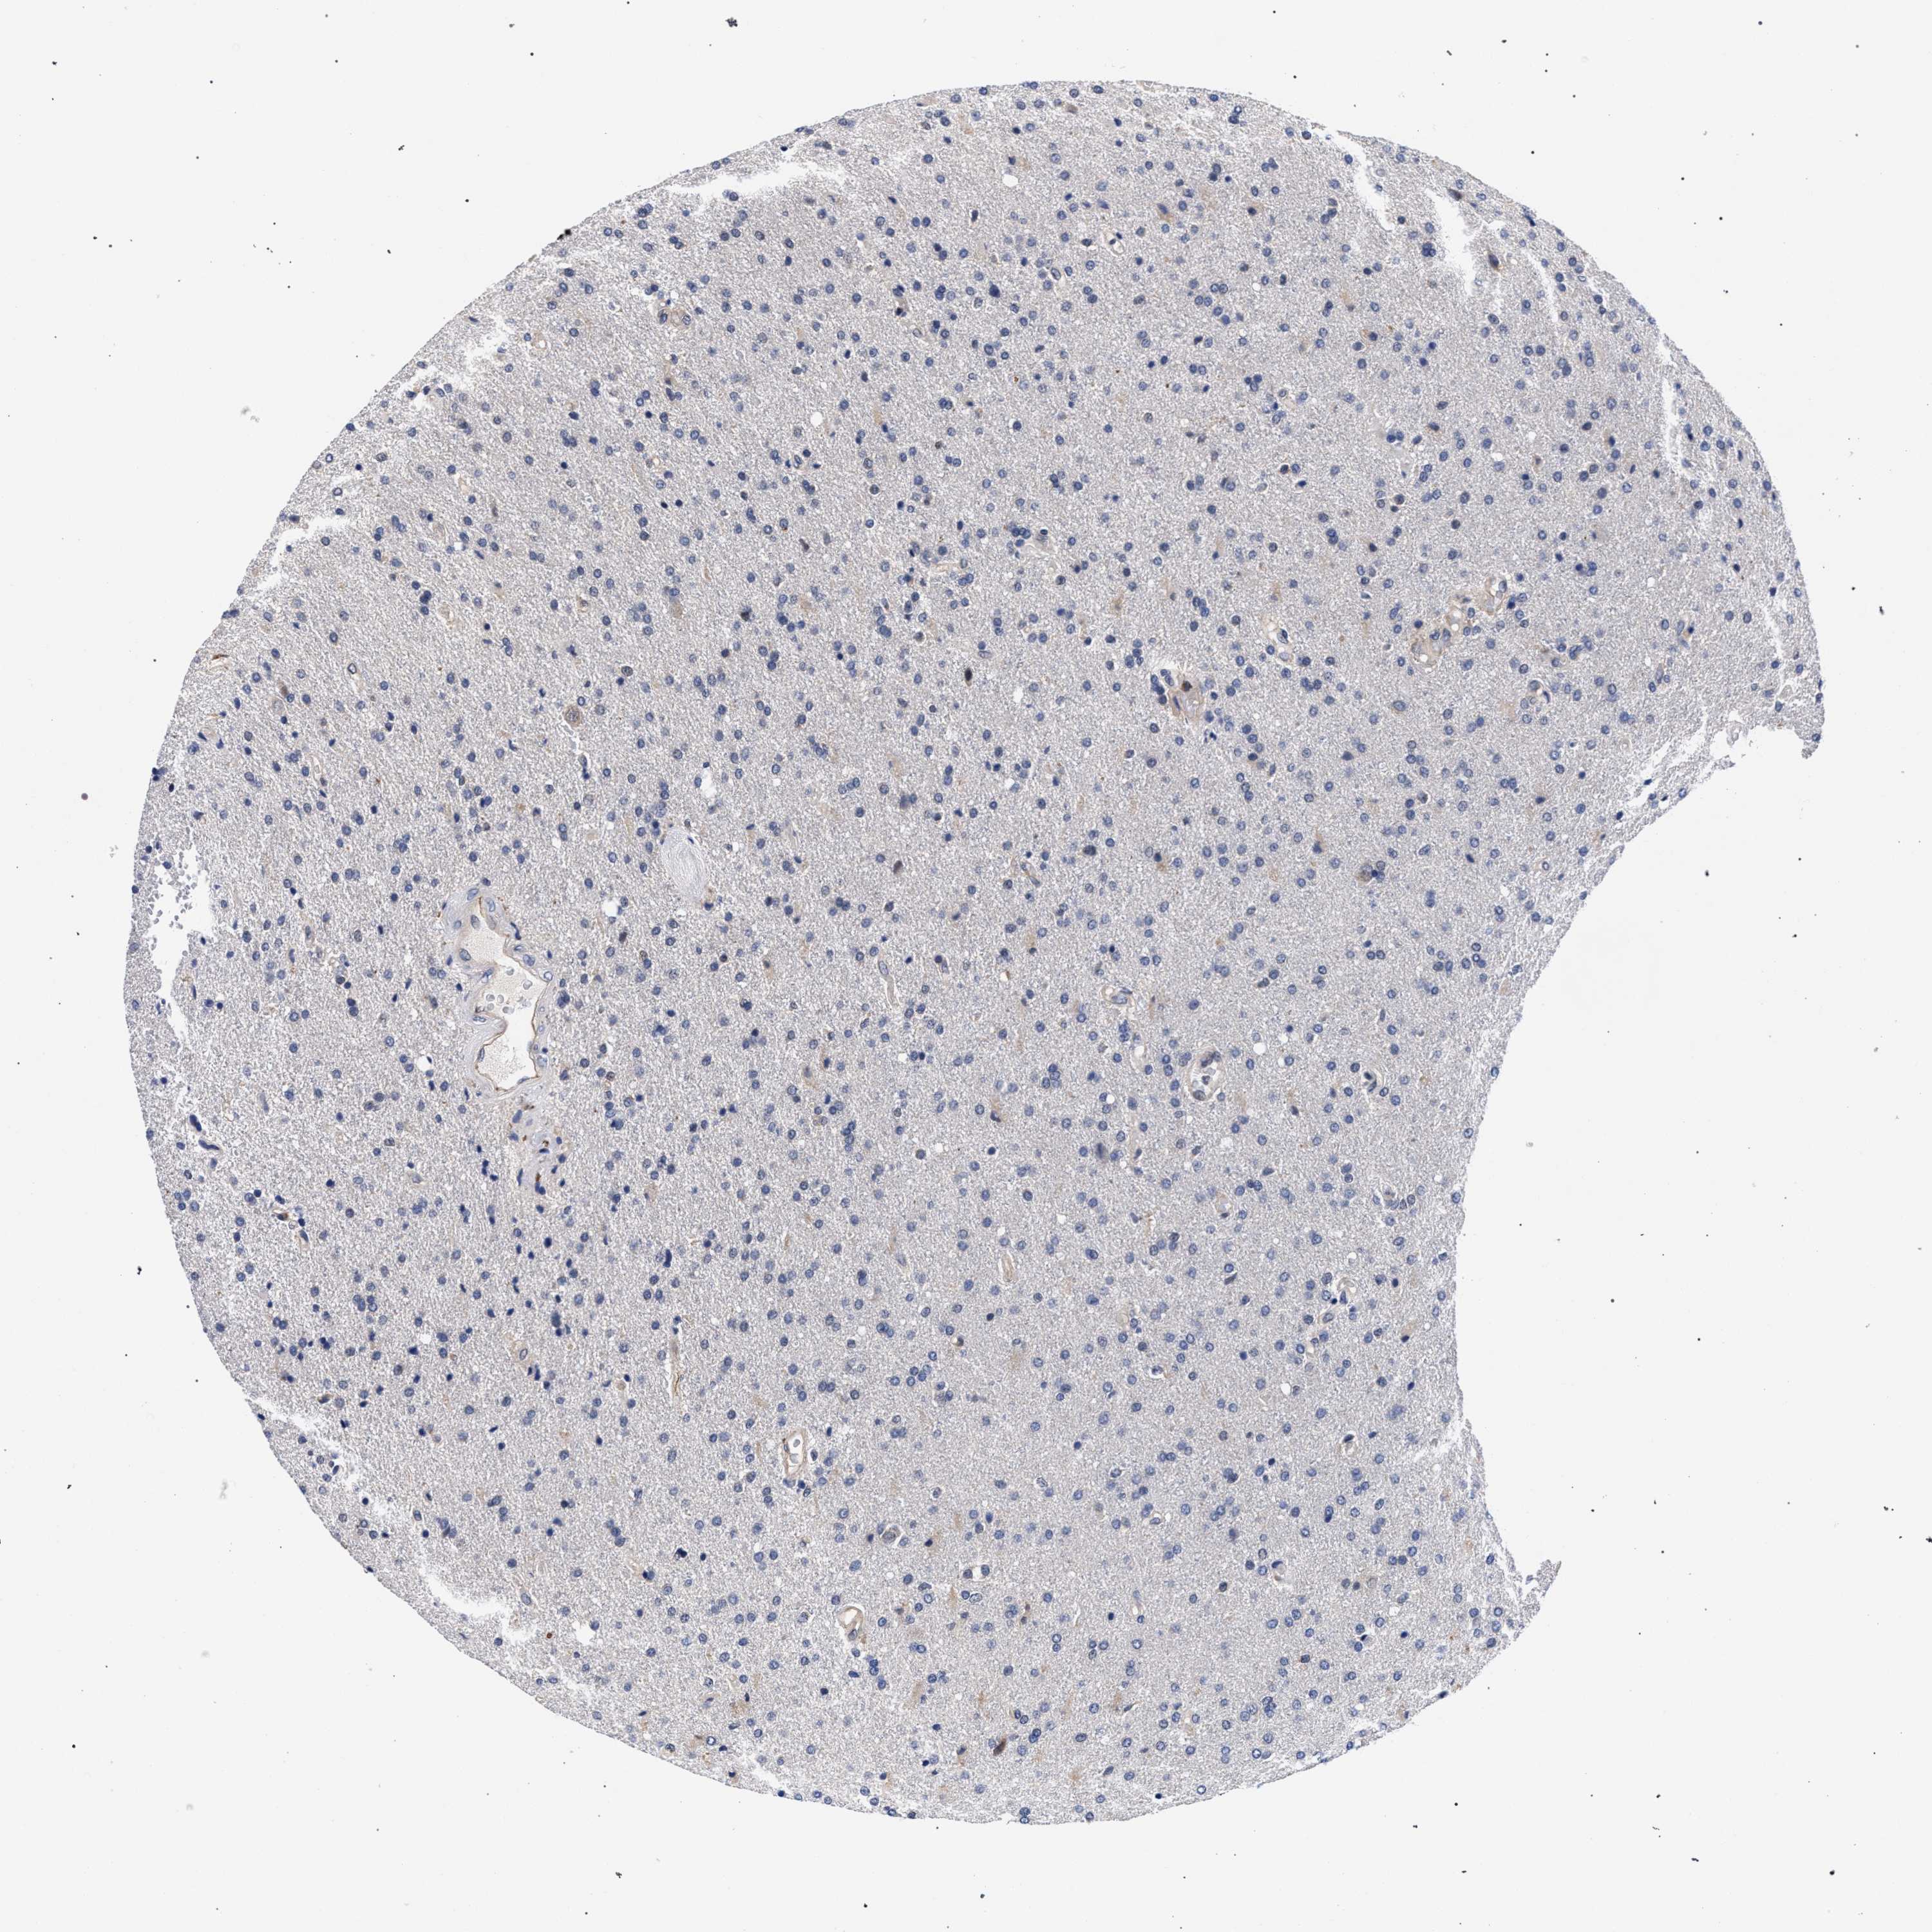

GLIOMA - Protein expressioni

A mouse-over function shows sample information and annotation data. Click on an image to view it in a full screen mode. Samples can be filtered based on level of antibody staining by selecting one or several of the following categories: high, medium, low and not detected. The assay and annotation is described here.

Note that samples used for immunohistochemistry by the Human Protein Atlas do not correspond to samples in the TCGA dataset.

Antibody stainingi

Antibody staining in the annotated cell types in the current human tissue is reported as not detected, low, medium, or high, based on conventional immunohistochemistry profiling in selected tissues. This score is based on the combination of the staining intensity and fraction of stained cells.

Each image is clickable and will lead to virtual microscopy that enables deeper exploration of all samples and also displays staining intensity scores, fraction scores and subcellular localization as well as patient and tissue information for each sample.

Antibody HPA019232

Antibody HPA021497

Antibody HPA021768

Staining

High

Medium

Low

Not detected

Intensity

Strong

Moderate

Weak

Negative

Quantity

>75%

75%-25%

<25%

None

Location

Nuclear

Cytoplasmic/membranous

Cytoplasmic/membranous,nuclear

Glioma, malignant, High grade

Glioma, malignant, Low grade